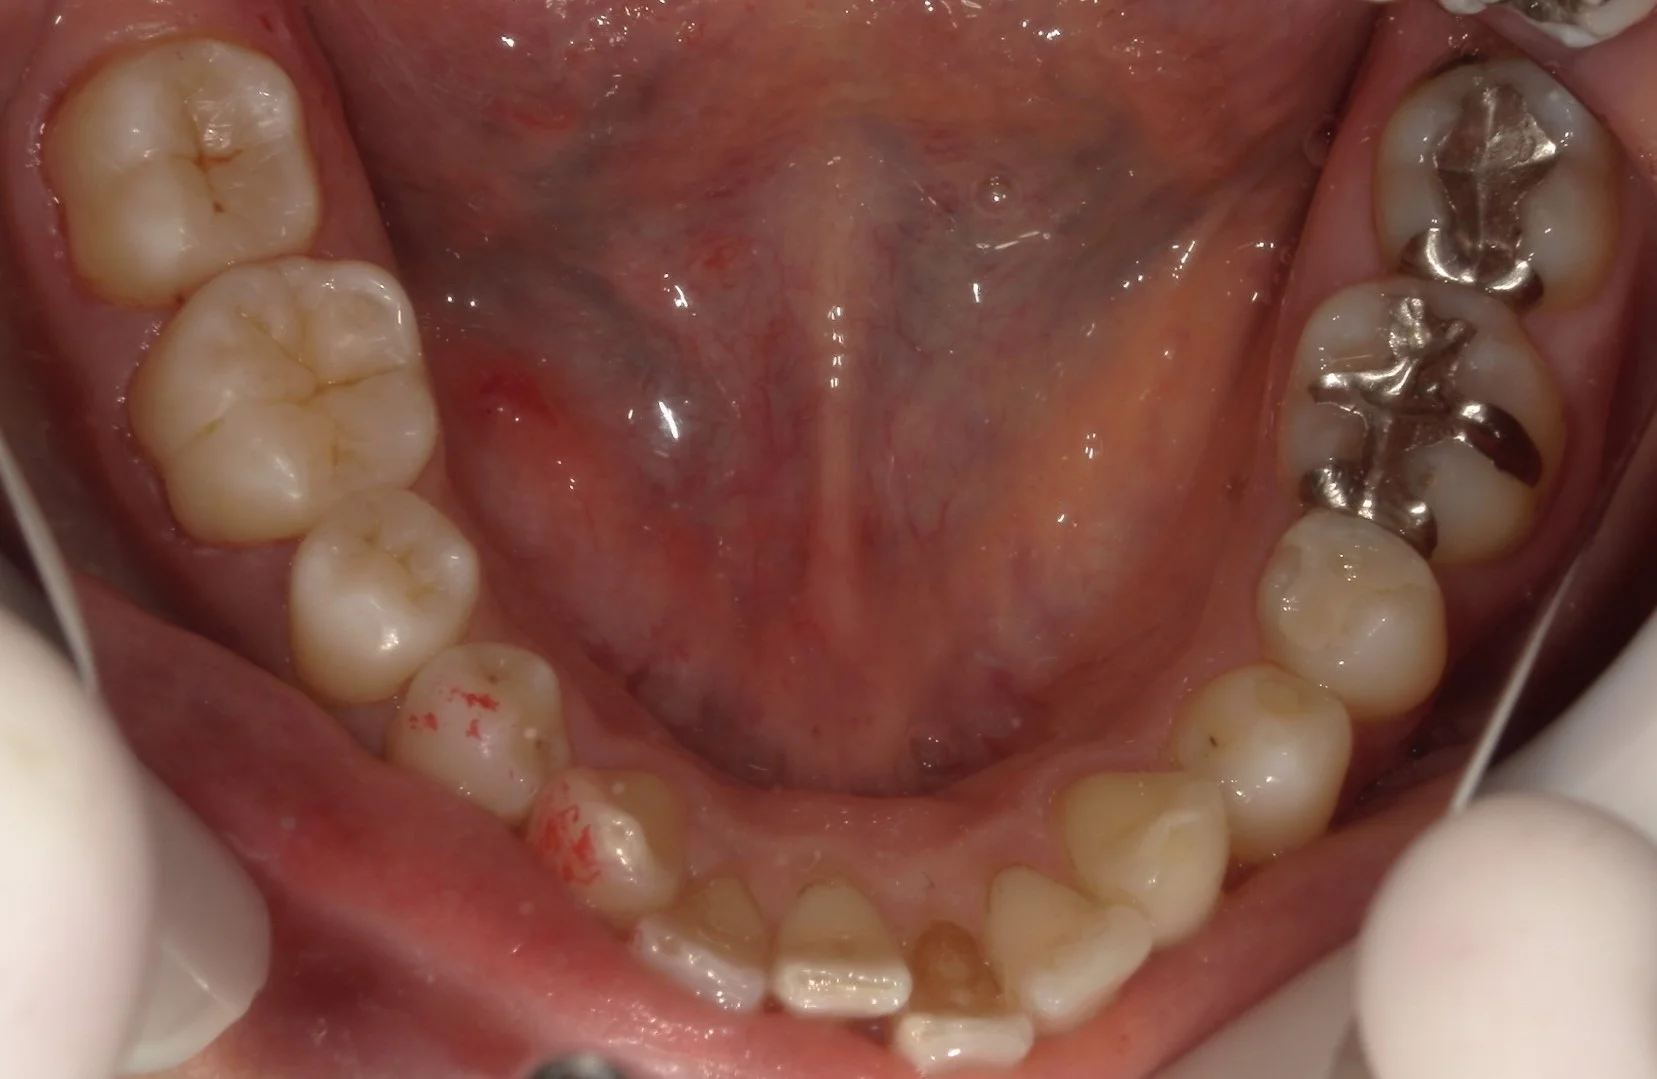

まずは術前ですね。

こちらの金属が入っている3本が治療予定の歯です。

右の2本については金属の下のみならず、根本の歯茎辺りにも虫歯があり、非常に広範囲となっています。

また、真ん中の金属については、金属の周りが咬耗と言って、歯が多く削れている状態になっています。

少量であれば削ったりする必要はないのですが、これほど深く削れている場合は、治療する際に邪魔してくることが多いので、今回は一緒に治療することとしました。